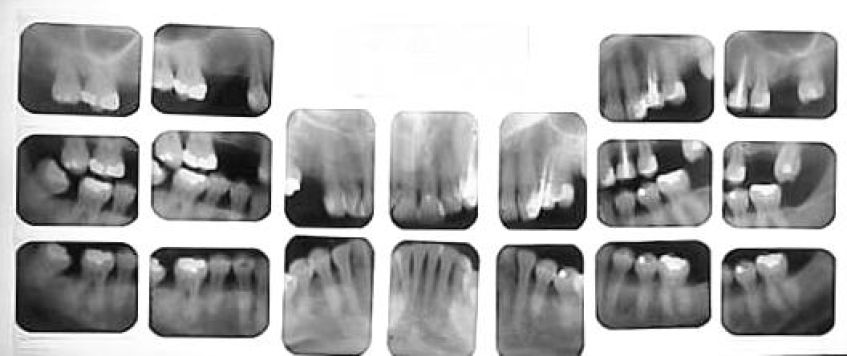

Дентальный рентгенаппарат (радиовизиограф) используется в том случае, когда необходимо сделать прицельный снимок одного или нескольких зубов. Большое контрастное изображение на экране компьютера, а также возможность трёхмерной визуализации полученных снимков способствуют постановке точного, безошибочного диагноза стоматологом.

Дентальные снимки необходимы при лечении корневых каналов зубов, диагностике кариеса между зубами и под деснами, а также вторичного кариеса под пломбами и коронками.

Дентальные снимки